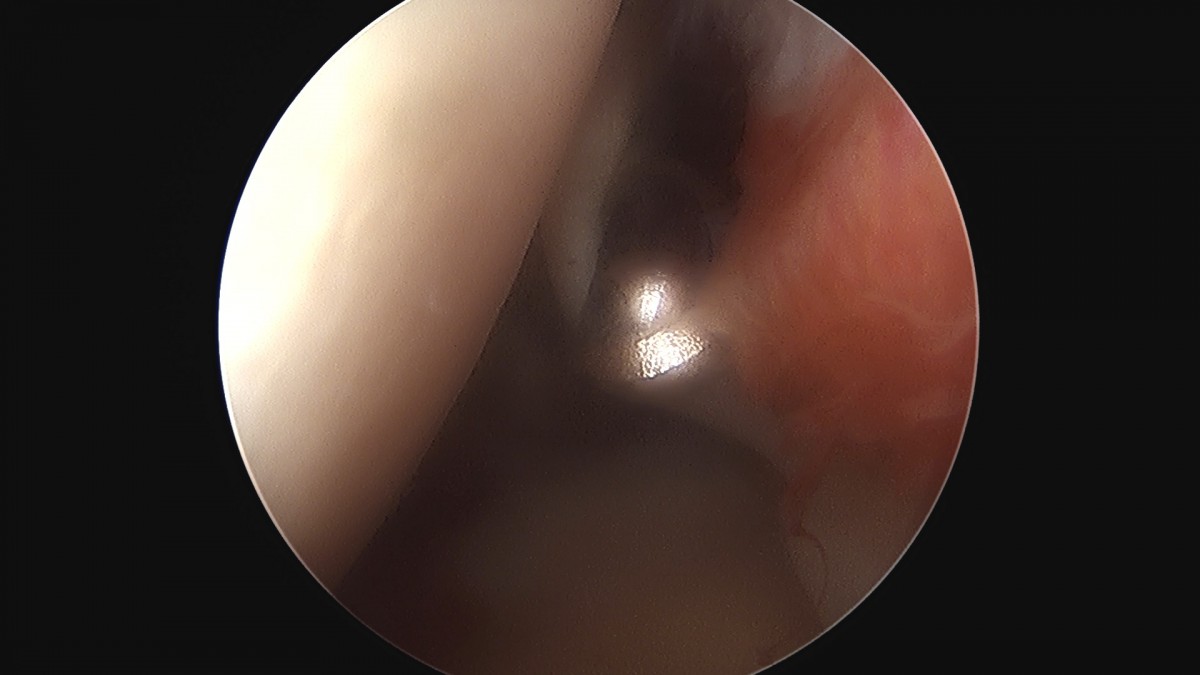

이재상원장님 어깨 견봉하 감압술 김봉O 환자

dae765e4d9ac96aee867c9d6292d8784_1758004119_985.jpg